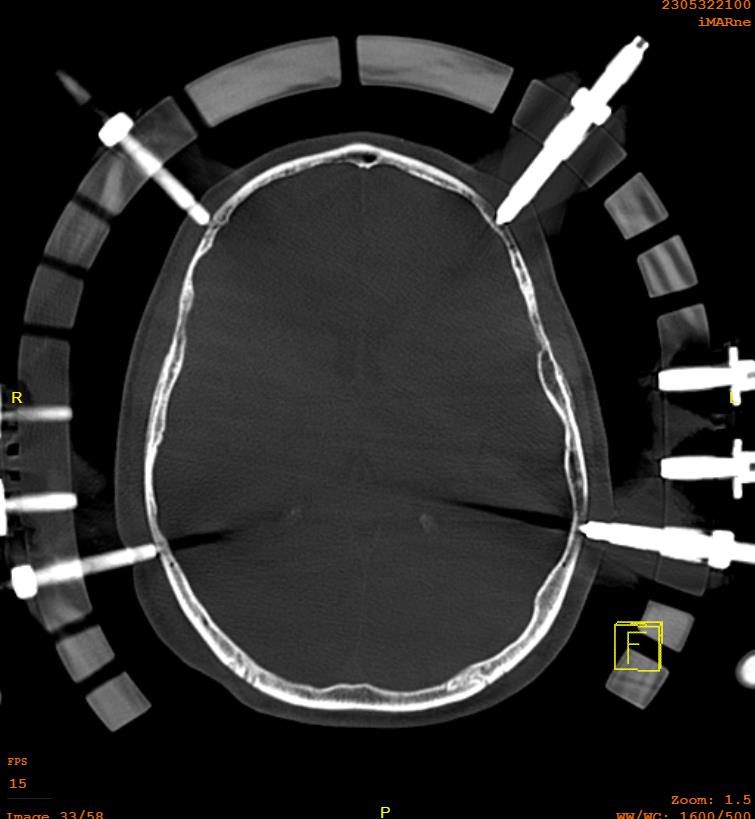

Pin safe zones

Frontal cranium

- above lateral 2/3 of the orbital rim / eyebrow

- 1 cm above top of ears

- medial to this zone is supraorbital nerve and frontal sinus

Technique

Halo

- size halo around maximum diameter of skull

- should have 1 - 2 cm gap from skull

- sits 1 cm above pinna and eyebrows

- 4 pins

- 2 above pinna, 2 above upper and outer eyebrow

- can shine torch through holes to mark sites of pins

- local anesthetic to sites

- must close eyes before supraorbital pins to avoid problems closing eyes

- tighten to 8 pounds / square inch

- often come with snap lock pins